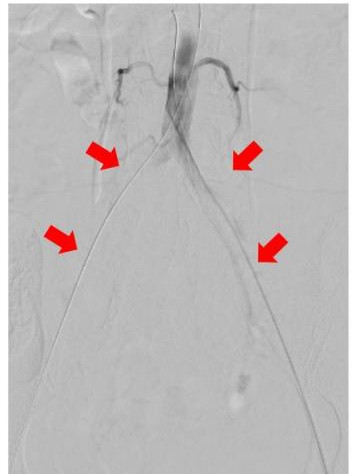

圖中箭頭所示:術(shù)前CTA提示腹主動(dòng)脈雙髂動(dòng)脈騎跨栓,腹主動(dòng)脈下段及雙髂動(dòng)脈血流中斷